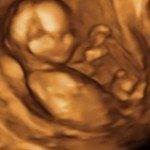

4D/5D/HD Ultrasound Gallery

Gallery